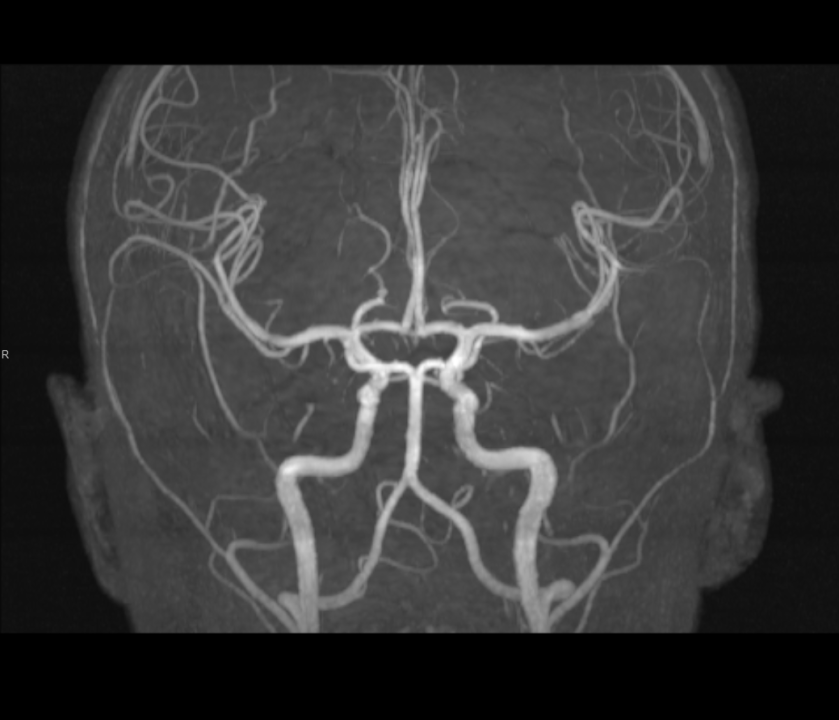

Tijekom Tjedna mozga Poliklinika Affidea Vita daje 20 posto popusta na magnetsku rezonancu!

Povodom obilježavanja Tjedna mozga od 11.